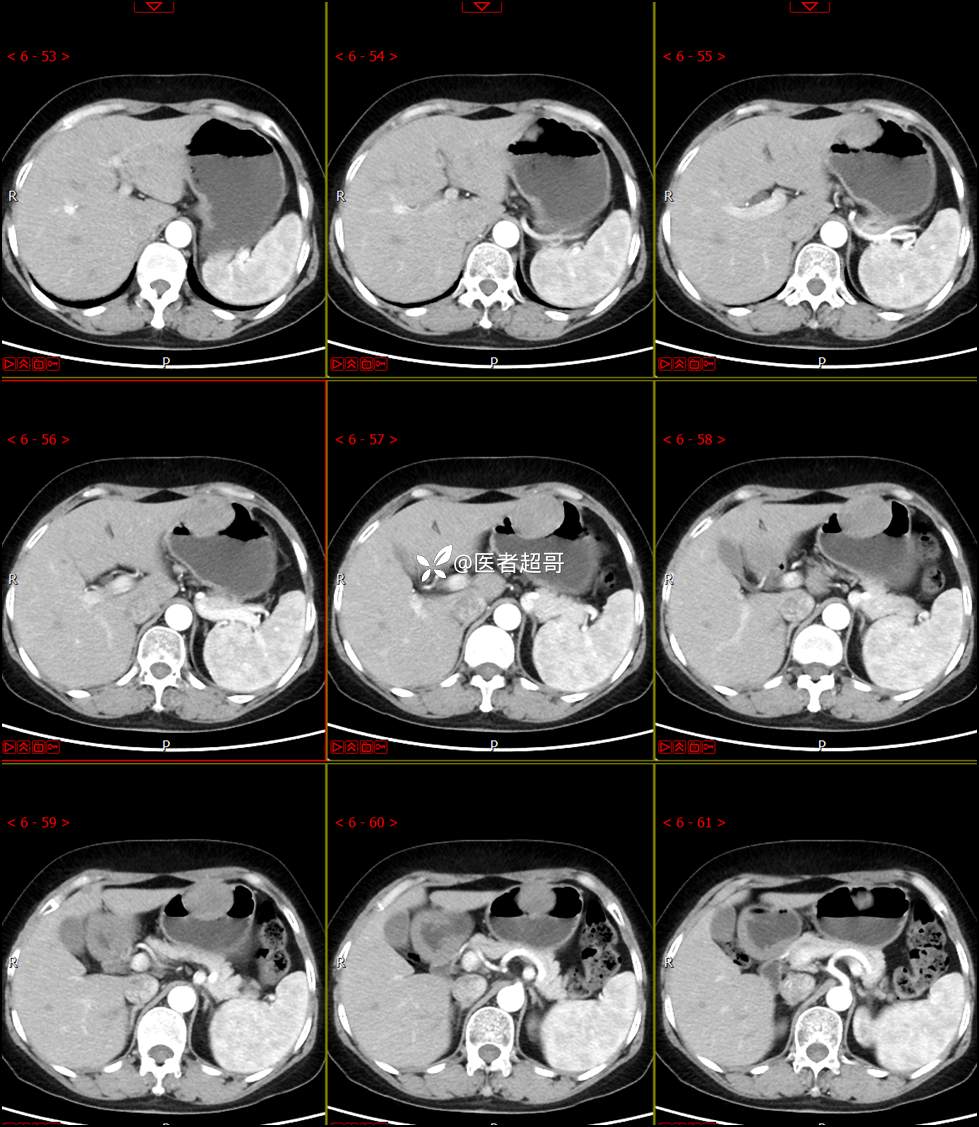

【影诊笔记759】胃体巨大隆起,间质瘤?神经鞘瘤?平滑肌瘤?请鉴别诊断!有结果!

患者半月前无明显原因及诱因出现上腹部疼痛不适,以夜间腹痛为主,无放射性疼痛,间断嗳气,无反酸烧心,无腹泻黑便,于我院门诊行胃镜显示:胃体前壁巨大隆起型病变。